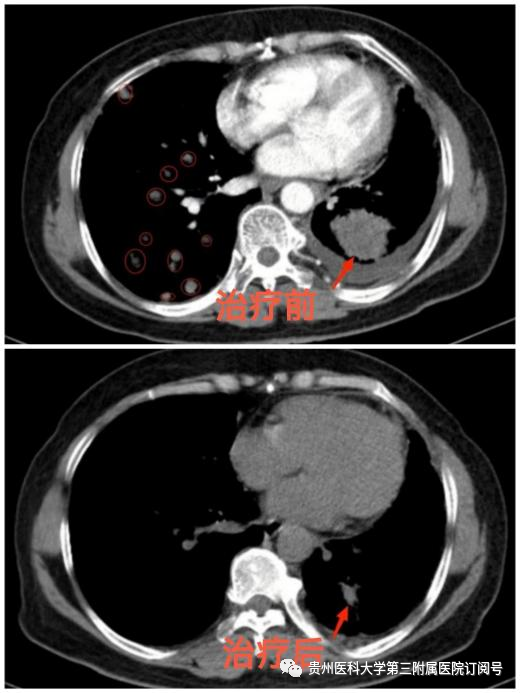

功夫不负有心人,经过肿瘤科的精心治疗和悉心护理,黄女士咳嗽、咳痰、胸痛、胸闷及呼吸困难已基本缓解,复查胸部CT提示多处病灶均较前明显缩小,精神状态明显好转。